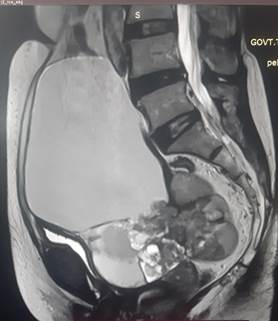

large abdominopelvic multilocular cystic lesion which was likely of pelvic origin . An MRI pelvis followed which revealed

a large abdominopelvic cystic lesion of 12.8 x11.7x 15.2 cm with multiple

internal septation (Ovarian-Adnexal Reporting and Data System - O- RADS 5 )

with mild ascites and no evidence of pelvic lymphadenopathy (Figure1).

Figire 1. MRI pelvis showed an abdominopelvic cystic

lesion.